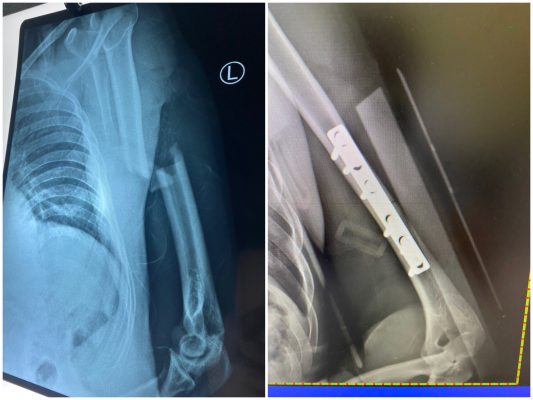

Phẫu thuật kết hợp xương cánh tay

Gãy xương cánh tay là một chấn thương phổ biến xảy ra ở cả trẻ [...]